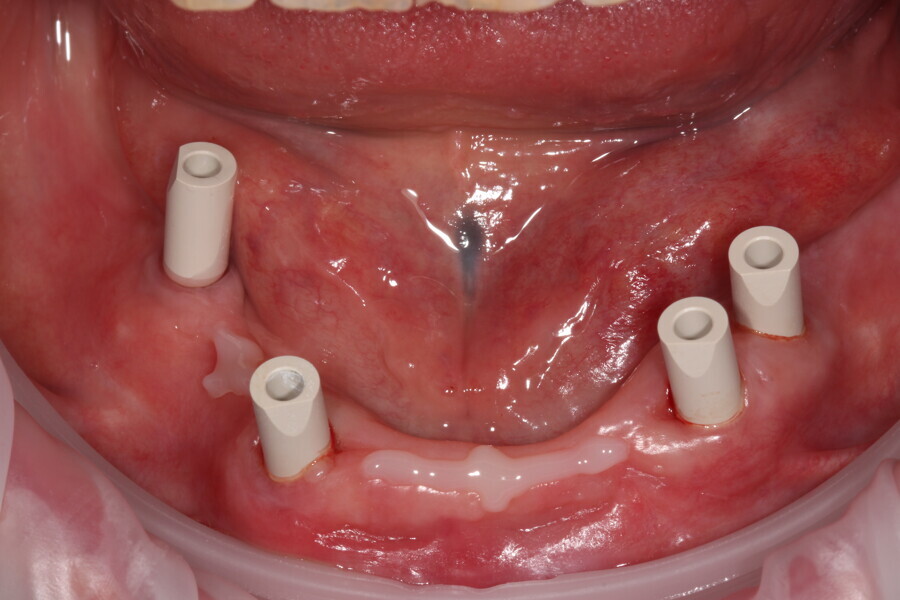

Fig. 10: Scanbodies in situ.